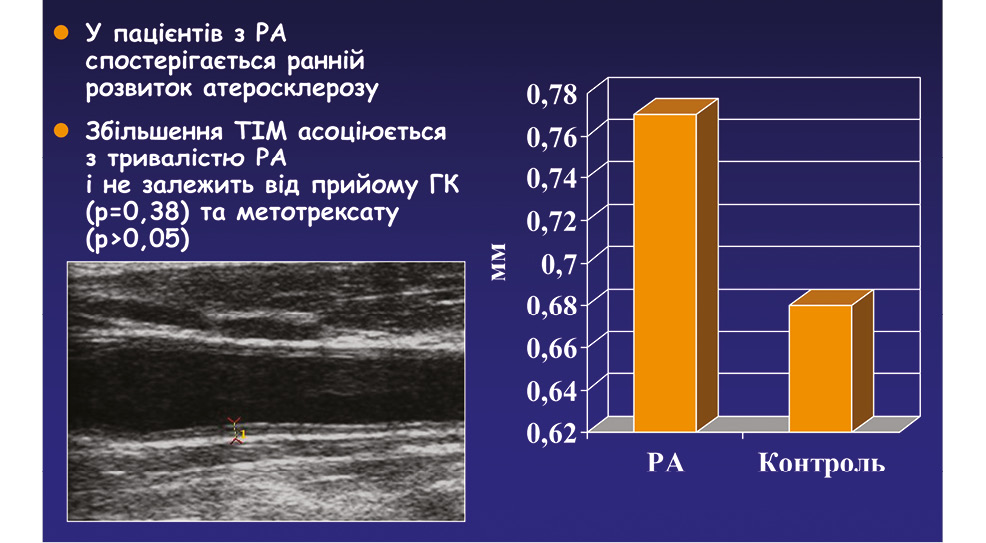

Рис. 6.

Товщина комплексу інтима–медіа (ТІМ) при РА та в контролі (дані УЗД) (Гарміш О.О., Левченко В.Г., Мітченко О.І., 2016)